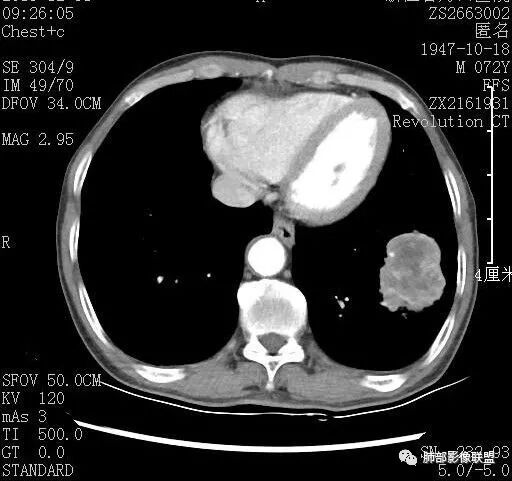

看纵隔窗及增强,内部无正常血管走行,支气管截断,偏心空洞,弥漫边界不清坏死,支持恶性,综合一下,癌(鳞?)>结核

右肺下叶肿块,分叶,近端支气管部分堵塞,部分沿壁厚,沼泽样强化,可见空洞,邻近胸膜少量积液,膈肌牵拉,考虑肿瘤,鳞癌?鉴别NTM

青年男性,慢性病程,右肺下叶团块影,形态不规则,内见空洞,壁厚薄不均,不均匀轻度强化。考虑恶性,肺癌,肿标中角蛋白19增高,倾向于鳞癌,鉴别结核。

中年男性,有咳嗽咳痰病史俩月,亚急性病程,炎性指标不高,右肺下叶后基底段近胸膜下不规则肿块,边缘膨隆毛糙,支气管近端阻塞,内有厚壁空洞,无液平,洞壁不均匀强化,周围支气管壁厚,远端有点片影,考虑鳞癌可能性大,鉴别肺脓肿和肺结核。但是血沉不快,crp不高,有点不大符合炎性。

脐凹?边缘膨隆

边缘膨隆,血管走形其中似远端破坏

看一下病灶主体,支气管堵塞

1.支气管截断

2.边缘模糊磨玻璃。

3.形态主体有明显膨隆,边缘有很多散发的病变边缘平直

4.远端有树丫,提示炎症一定存在的

5.淋巴结稍大

6增强后有很多坏死,与实性成分分界不清

7.脐凹?